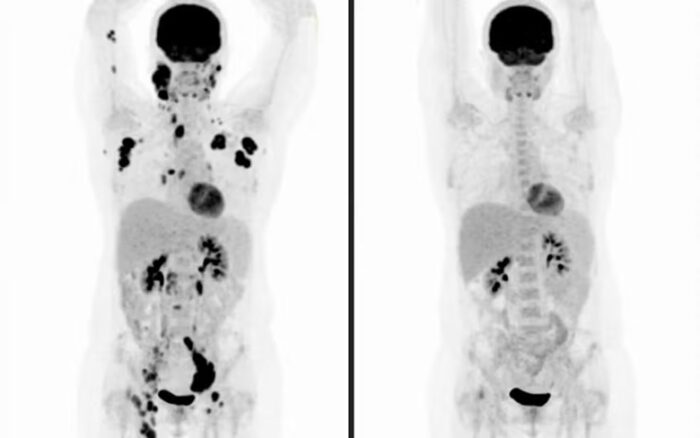

Publicada no “Journal of Medical Economics”, a pesquisa analisou o impacto clínico e financeiro do uso dessa tecnologia em pacientes com linfoma difuso de grandes células B, o tipo mais comum e agressivo de linfoma não Hodgkin.

A terapia celular CAR-T é uma forma avançada de imunoterapia personalizada. As células de defesa do paciente (linfócitos T) são retiradas do sangue, modificadas geneticamente em laboratório — fora do Brasil — para reconhecer e atacar o tumor, e depois reinfundidas no corpo.

A tecnologia está aprovada no Brasil pela Agência Nacional de Vigilância Sanitária (Anvisa) para tratar linfomas e leucemias que não respondem a terapias anteriores. As versões disponíveis são o axi-cel (axicabtagene ciloleucel), o tisa-cel (tisagenlecleucel) e o cilta-cel (ciltacabtagene autoleucel, usado em mieloma múltiplo).

Antes da chegada da CAR-T, as taxas de cura para o linfoma difuso de grandes células B recidivado não passavam de 20%.

Com a nova terapia, os índices de cura e sobrevida sobem para 50% a 60% em dois anos, segundo o levantamento.

“Estamos curando de 30% a 40% a mais de pacientes. É uma mudança real no destino dessas pessoas”, afirma Nabhan.